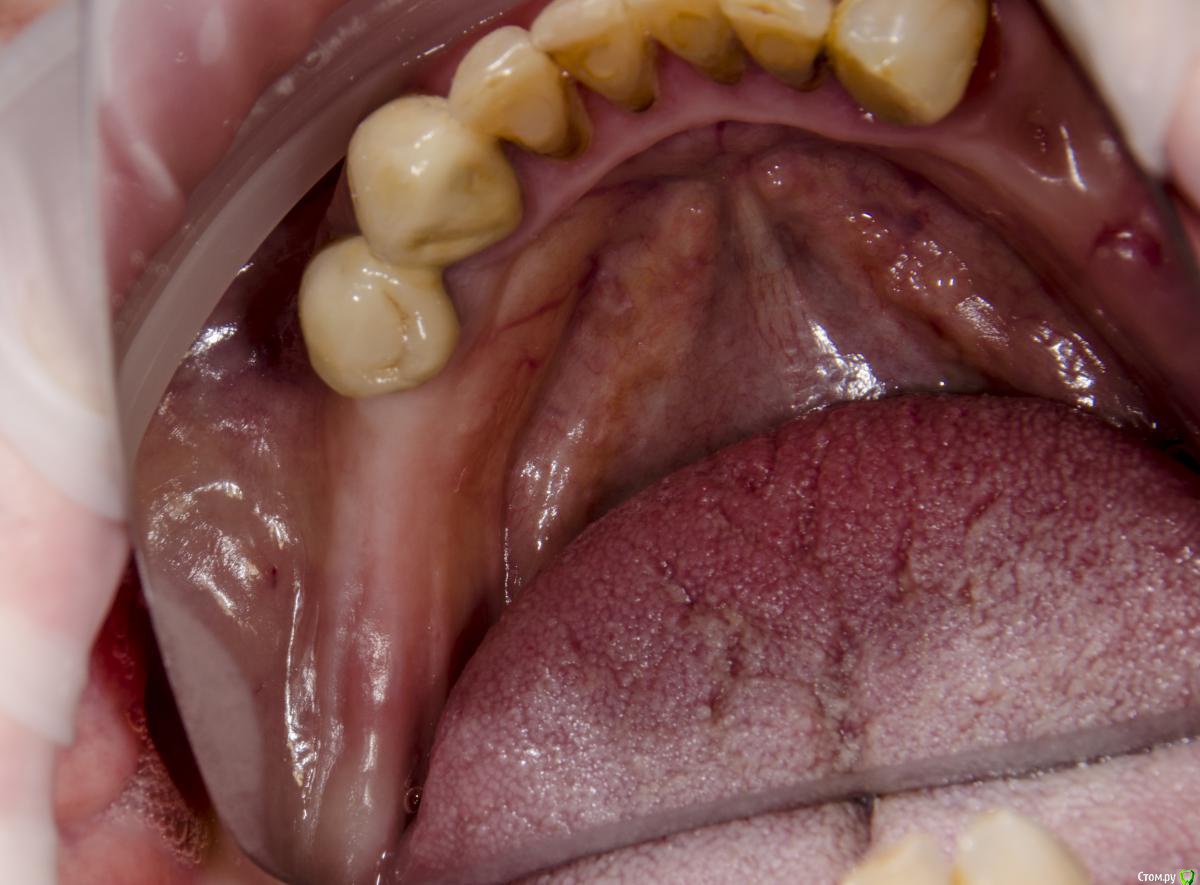

kamranchick Опубликовано 12 сентября, 2015 Поделиться Опубликовано 12 сентября, 2015 Доброго всем дня и хороших выходных)вопрос следующего планаПациент обратился с жалобами на отсутствие зубов пациент среднего достатка.начали потихоньку работать, сверху все зубы удалили, начали имплантирование снизув области 4 сегмента установили 2 имплантата в области 45 46, так как условия неплохие, в области 7 зуба начинается скос, ну и придется либо заваливать имплантат язычно либо делать пластику, как Вы думаетестоит ли вкручивать имплантат в область 7 зуба?тогда наверное и с другой стороны придется вкручивать, так как там отсутствует 4567зуб, ну а сверху как вы поняли зубов нету уже, ни одного)кт если кому то понадобятся. срезу кину в в в будние дни) Ссылка на комментарий